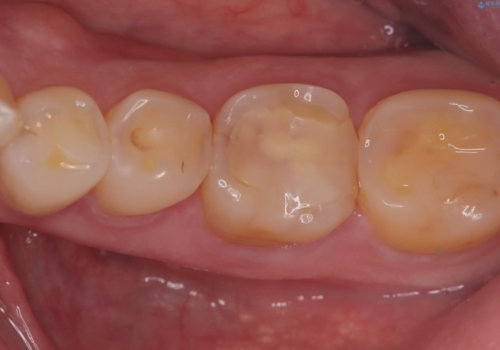

よく見ると歯冠部に咬合面から近心側にのびるヒビ(クラックライン)が入っているのが見えます。

各種検査を行い、咬合面にヒビ(クラック)を認めました。

元々咬合面にレジンインレーが入っており、近心歯質が薄くなっていたことや、食いしばるクセを持っていることも、ヒビが入った要因の一つと考えられます。